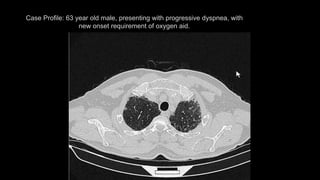

Case Profile: 63 year old male, presenting with progressive dyspnea, with

new onset requirement of oxygen aid.

Case Profile: 63year old male, presenting with progressive dyspnea, with new onset requirement of oxygen aid.